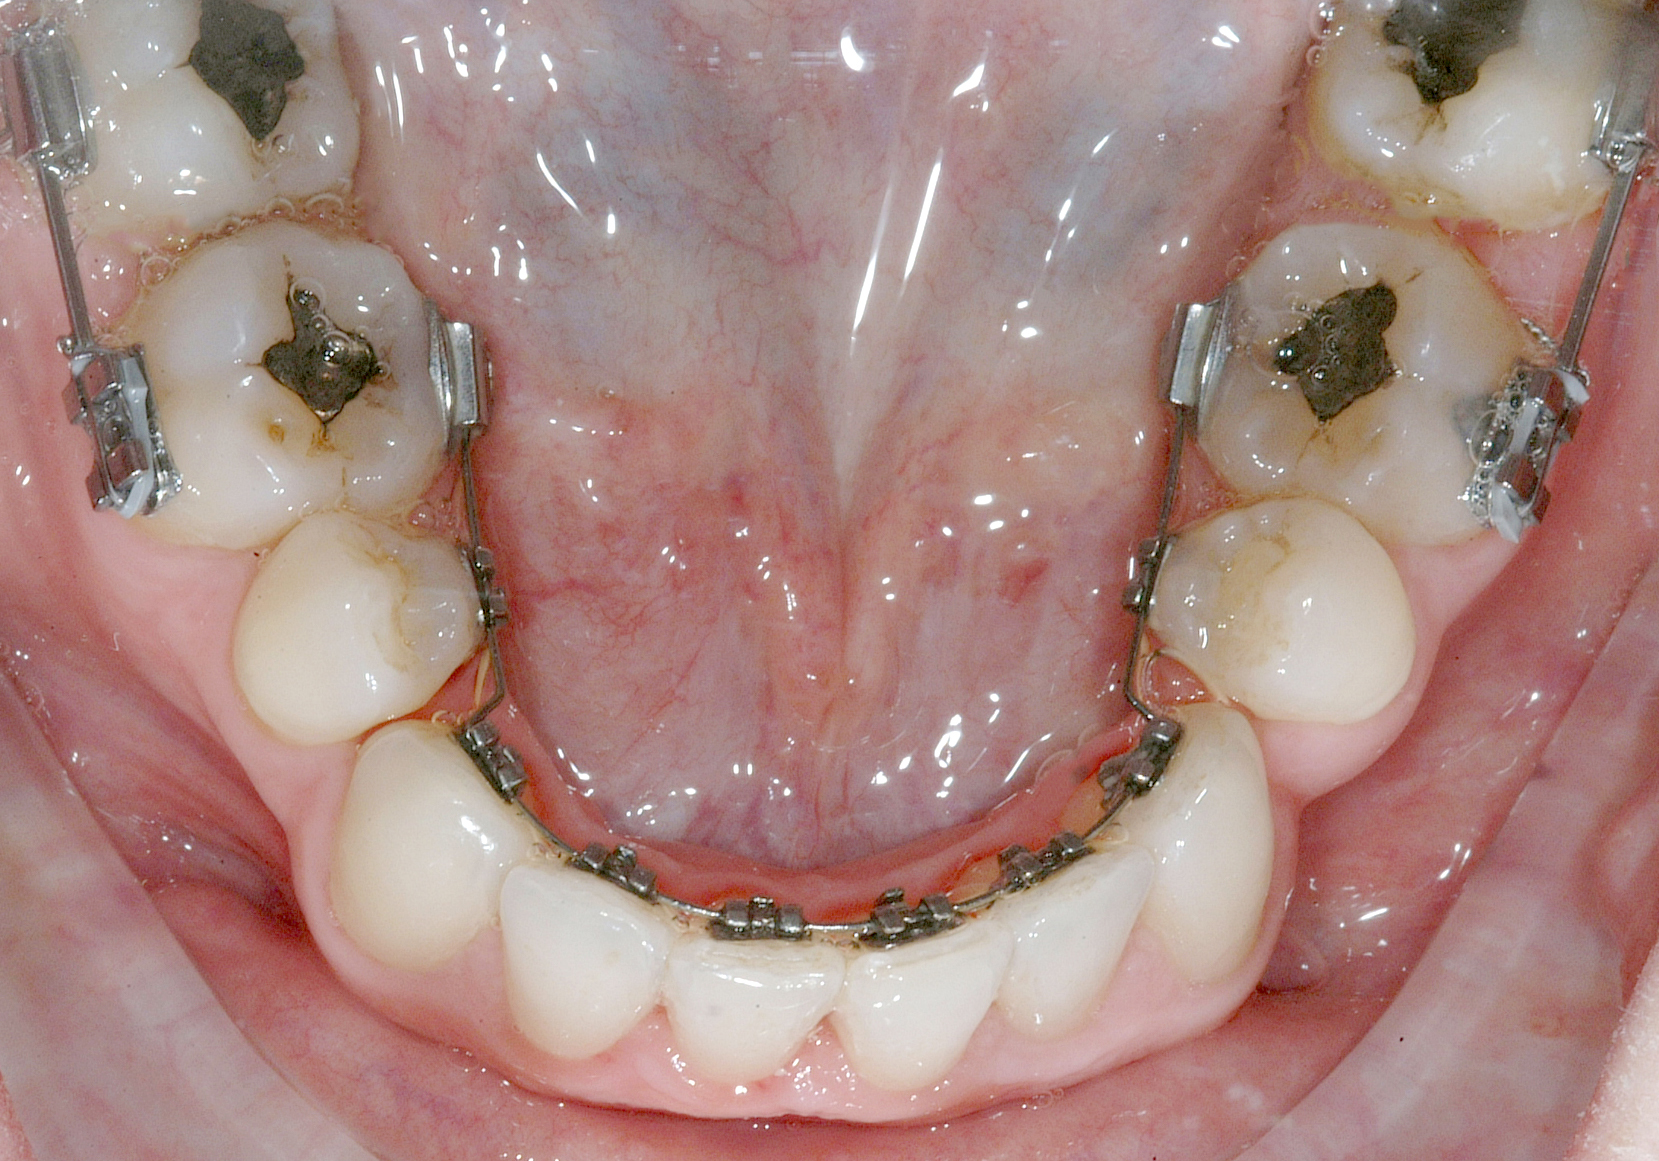

Il protocollo terapeutico ha previsto l’estrazione del primo premolare inferiore sinistro (3.4) e del primo superiore destro (1.4), l’applicazione di una apparecchiatura fissa linguale 2D e di una meccanica asimmetrica di ancoraggio e movimento ortodontico a entrambe le arcate (Figure 3a-b).

Per la chiusura dello spazio all’arcata inferiore, dopo la preliminare fase di allineamento e livellamento2, con la stessa sequenza iniziale di archi (.014” e poi .016” Nichel-Titanio), è stato temporaneamente applicato un sistema di ancoraggio ausiliario vestibolare, mediante fibre rinforzate, bondate sulla superficie vestibolare di 3.5, 3.6, 3.7 (Figura 4).

Successivamente, per controllare il movimento radicolare distale del canino inferiore sinistro (3.3), è stato applicato un sistema di forze che ha sfruttato: la forza singola distalizzante e di chiusura spazi data dalla catenella elastica con ruolo stabilizzante anche verticale su 3.3, inserita e agganciata in due segmenti, uno mesiale e uno distale, nelle rispettive alette dello slot occlusale del 3.3, e una coppia di forze di uprighting data dall’arco ortodontico .016” Nichel Titanio; quest’ultimo è stato inserito distalmente nello slot ausiliario dell’attacco linguale sul 3.5 ottenuto ripiegando verso occlusale la terza aletta gengivale, e poi nel tubo singolo sul 3.6, e mesialmente, da mesiale verso distale e da gengivale verso occlusale nello slot di 3.3, generando una flessione verticale di secondo ordine, la cui rotazione in senso linguale veniva controllata dalla catenella elastica stessa in appoggio su di esso. Il segmento di arco distale a 3.2 è stato ripiegato in senso gengivo-vestibolare (Figura 5).

Nota tecnica: una volta ottenuto il corretto posizionamento del 3.3, al fine di simmetrizzare l’arcata inferiore e centrare le linee di simmetria, è stata applicata una molla ad anse aperte tra 4.4 e 4.3 su arco .016” in acciaio (Figura 6).